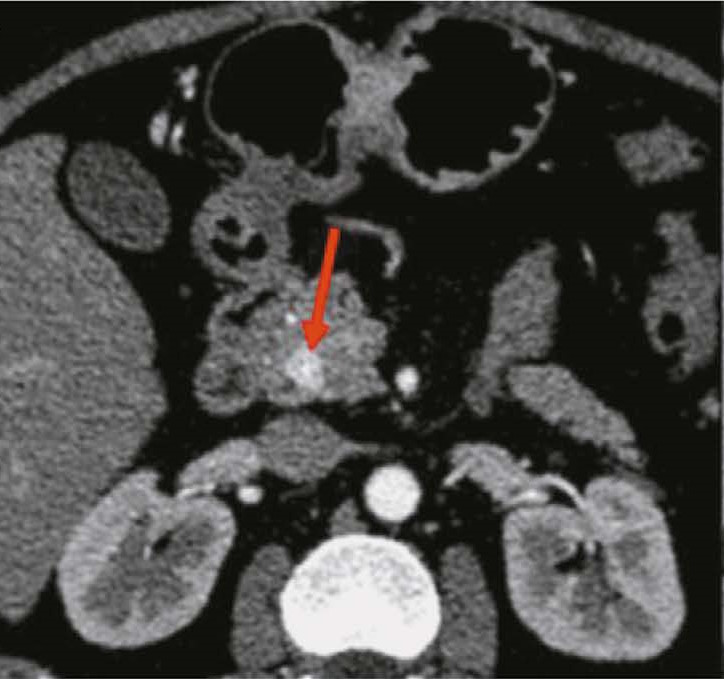

RESULTS: CT scan examples demonstrate typical and atypical visual signs of neuroendocrine tumors of stomach and pancreas, contrast enhancement characteristics, location and structure of neoplasms. Fifteen radiomics parameters were identified that were statistically significantly different between gastric neuroendocrine tumor and gastric adenocarcinoma. In pancreas, neuroendocrine tumors differed significantly from adenocarcinomas in 14 radiomics parameters.

CONCLUSIONS: Neuroendocrine tumors of stomach and pancreas are rare neoplasms that are mostly asymptomatic and difficult to visualize due to their small size and contrast enhancement characteristics. Texture analysis may be a promising approach to differentiate gastrointestinal neuroendocrine tumors from other neoplasms at these sites, especially in the view of the difficulty in obtaining a biopsy.